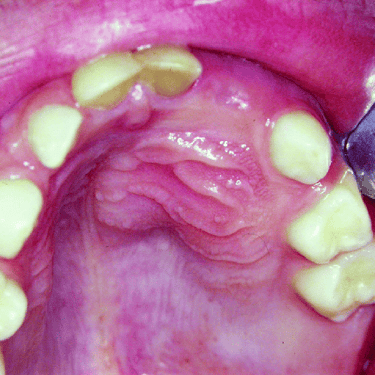

Dientes Supernumerarios

Los dientes supernumerarios son dientes adicionales que pueden aparecer en la boca y causar problemas de alineación o erupción de otros dientes.

Los pacientes pueden notar dientes adicionales en la boca, lo que puede causar apiñamiento o problemas estéticos.

El tratamiento incluye la extracción quirúrgica de los dientes supernumerarios.